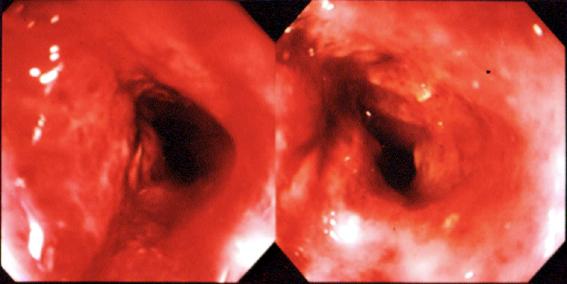

질환(병리주체)의 분류 악성 상피성종양/선암

부위(장기별) 대장/횡행

검사방법 내시경

종양의 육안분류 4형(미만침윤형)/

종양의 최대경(밀리미터) 40이상

종양의 심달도 s(a)